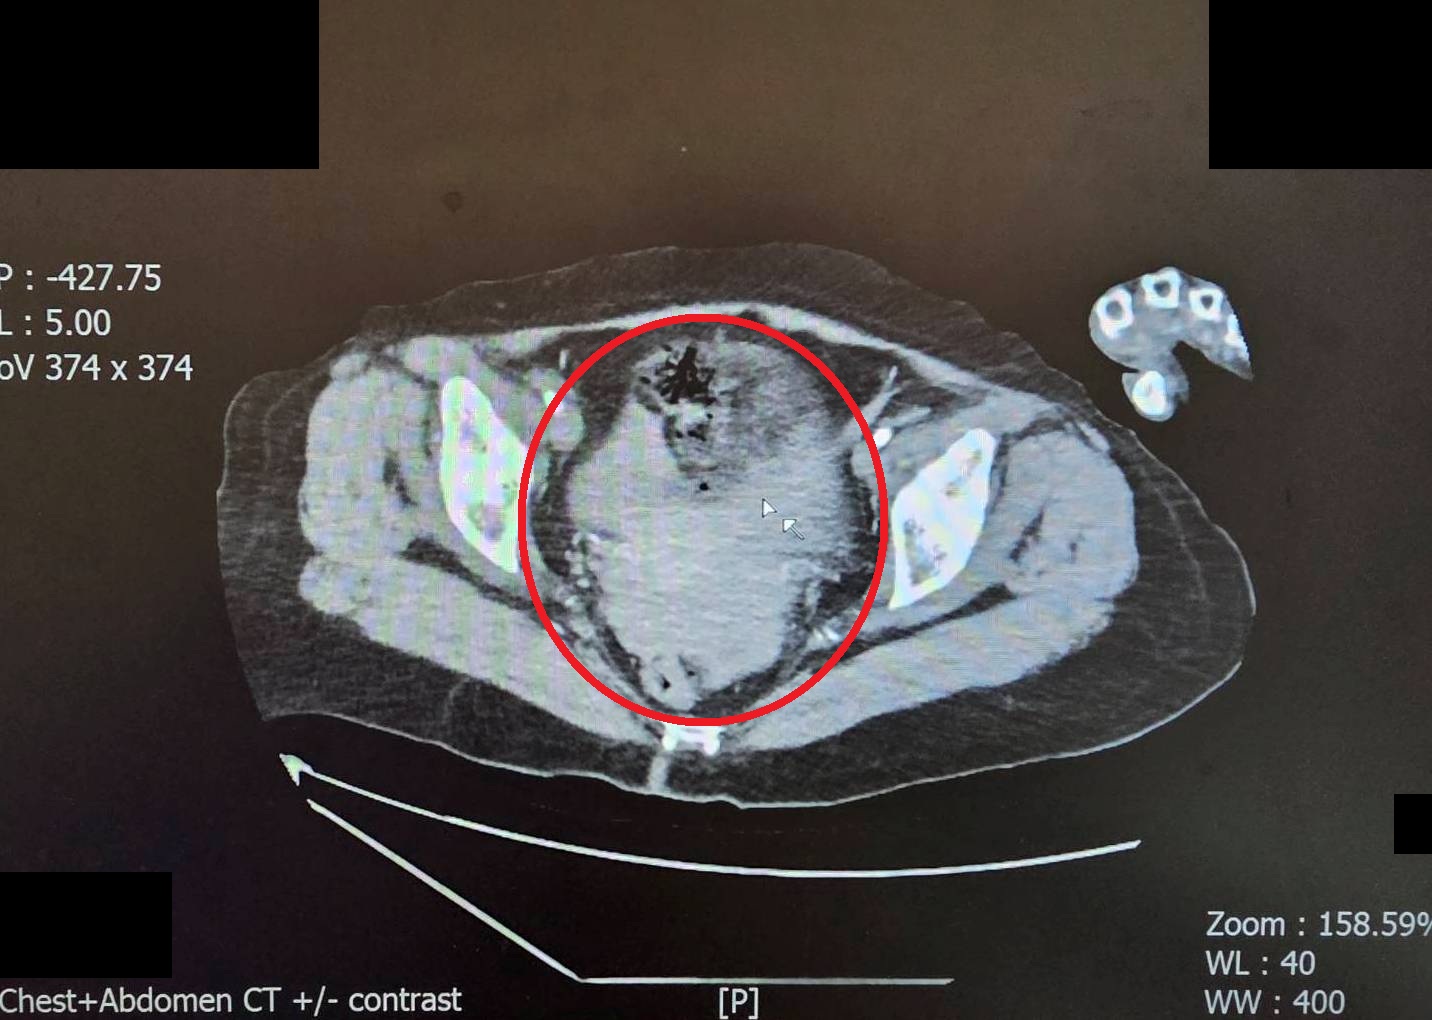

陳姓女子被送抵急診時,出現嚴重的雙側氣胸與皮下氣腫,呼吸極度困難。經全身電腦斷層掃描發現,強大的撞擊力導致她的左側橫隔膜破裂,原本應在腹腔的胃部及部分腸道,竟位移進入左側胸腔,嚴重壓迫左肺,導致肺部無法擴張。此外,檢查更發現其下腹部大量出血(腸繫膜血管破裂)、左腳踝骨折,背部還有大面積的2至3度擦燙傷,傷勢遍布全身。